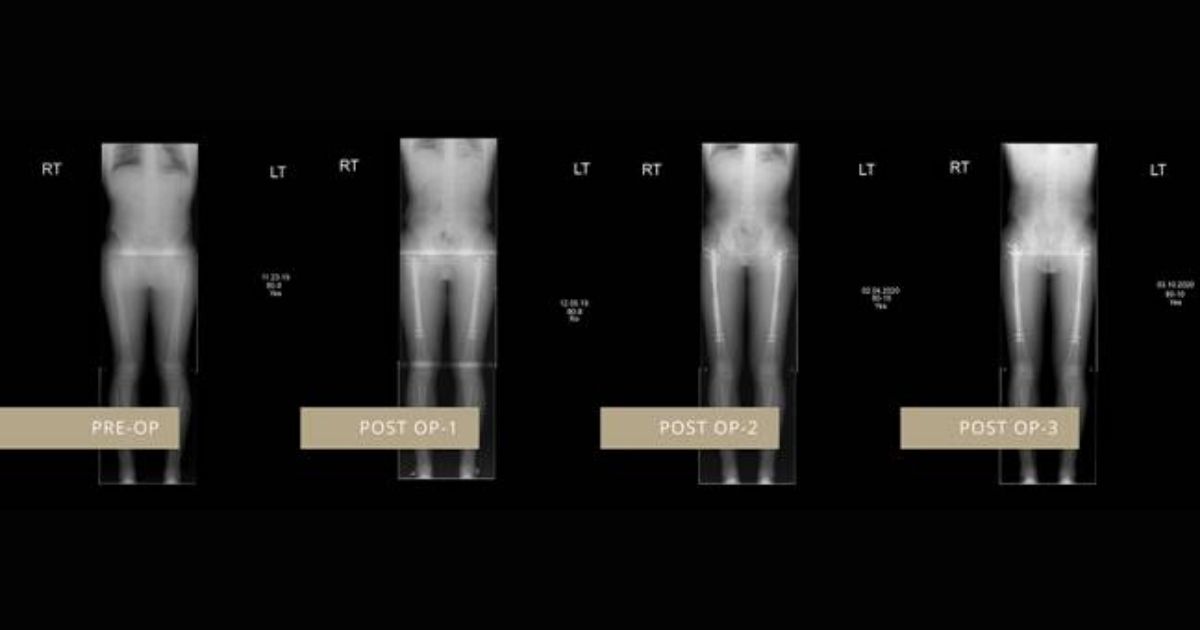

One patient praised the height treatment and said that it gave a huge boost in his confidence. The patient is Irving Rodríguez, a plastic and reconstructive surgeon, was 5ft 4in tall when he first visited LimbplastX Institute in Las Vegas in December 2019, but six months later he now stands at 5ft 6.7in.

“I had my surgery in December 2019 and my initial height was 165cm (5ft 4in). I chose The LimbplastX Institute as I knew that Dr. Debiparshad used the best technology to perform this procedure.”

“[The results] were evident very quickly after surgery. I started using the external remote control a couple of days after the procedure and it increased my height about 1mm a day until I reached my ideal height.”

“Patients can expect to gain up to six inches in height across two lengthening surgeries. This bone-lengthening process is usually painless, and the surgery takes about an hour and a half to complete.”